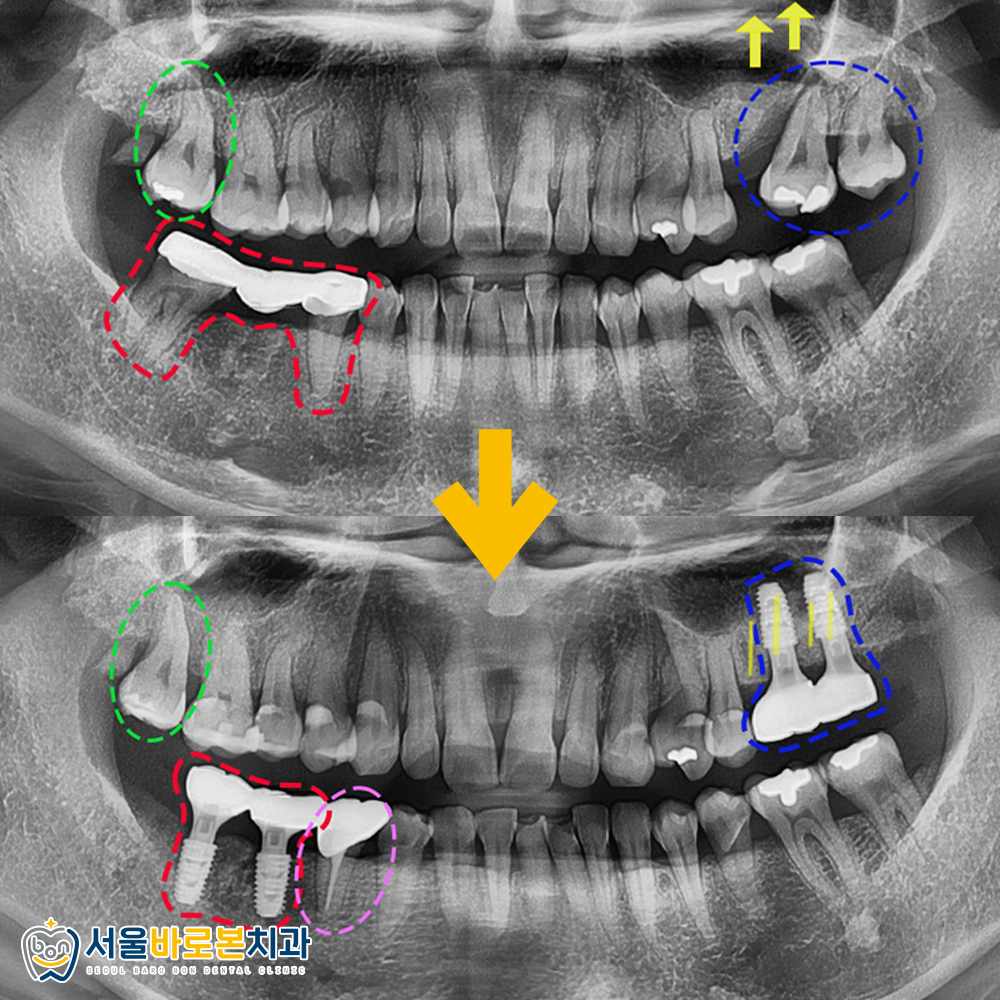

우선 정면 사진을 보시면,

📌 그리고 왼쪽 위의 어금니는 (파란색표시)

뼈가 많이 녹아 동요도까지 보이고 있어

발치 후 임플란트 식립이 필요하였습니다.

📌 오른쪽 위의 어금니는 (초록색표시)

과거 아말감을 진행한 치아 하방으로

2차 충치가 생겨 아말감 제거 후

인레이 치료를 진행하고,

📌 오른쪽 위의 어금니 부위에 보이는 충치들도

충치 제거 후 인레이 치료를

도와드리기로 했습니다.

📌 또한 불편을 겪고 계시던

오른쪽 아래는 (빨간색표시)

우선 브릿지를 제거하고

판단하기로 하였습니다.

파노라마 사진상에서도

한번 더 정밀하게 체크를 하였고,

치료계획을 환자분께도 설명드렸습니다.

그런데 왼쪽 위의 파란색 부위엔

바로 임플란트를 심기엔 어려움이 있어,

상악동 거상술 및 뼈이식이 필요해보였는데요!

현재 엑스레이 사진에는

치아 뿌리 역할을 하는

임플란트 픽스처만 식립이

되어 있는 상황인데요.

아래쪽 역시 픽스처가

잇몸뼈에 잘 고정된 것을 확인한 후

본을 뜨고, 크라운을 씌우는

보철작업을 마무리해드렸습니다!

이렇게 위 아래 임플란트 모두

📌 그리고 오른쪽 아래 브릿지의 지대치였던

두번째 작은어금니는

신경치료 후 크라운 수복을 진행하여

자연치를 살려드렸습니다. (분홍색표시)

📌 또한 2차충치가 있었던

오른쪽 위 어금니는 (초록색표시)

아말감을 제거 하고

인레이 치료를 도와드렸고,

📌 그 밖에 오른쪽 위의

충치가 있던 부위들은 인레이 치료를,

치경부 마모증으로 패여있던 부위들은

레진 수복을 하여 마무리해드렸습니다.